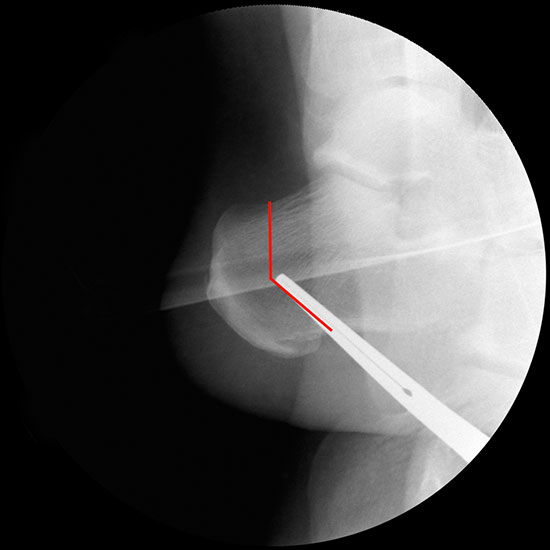

Bei Rückfussfehlstellungen ist meist eine knöcherne Korrektur des Kalkaneus indiziert. Dabei wird das Fersenbein im Bereich des Tuber calcanei durchtrennt und der Achillessehnenansatz nach medial oder lateral geschoben. Zusätzlich ist eine Rotation des Tuber möglich, wodurch sich der Korrektureffekt noch verstärkt. Durch die Wahl der Osteotomieebene kann die Verscheibung mit einer Verlängerung oder Verkürzung des Fersenbeins kombiniert werden. Die Osteosynthese erfolgt typischerweise durch perkutan eingebrachte Schrauben.

Durch eine V-förmige Schnittführung kann eine Translation des Tuber calcanei nach dorsal zuverlässig verhindert werden, bei hoher primärer Stabilität.

Abbildung 3